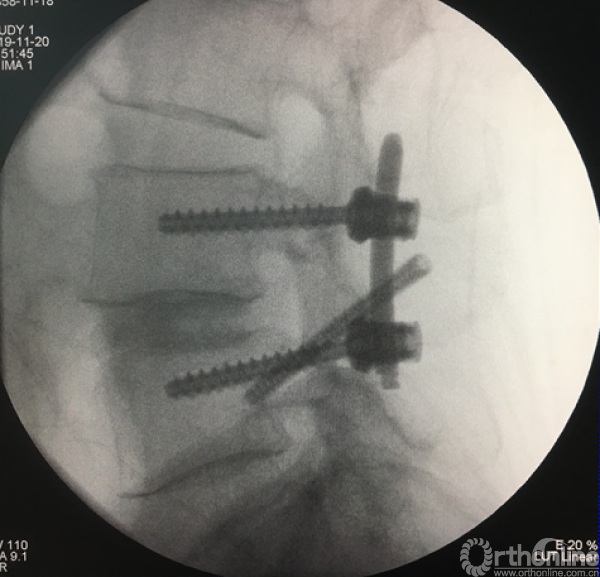

患者术后充分止血后,进行缝合切口、皮肤缝合。整个手术过程耗时2小时出血量在40-80毫升,术后不放置引流管,手术顺利。患者术后定制腰椎支具固定,24小时后下床活动、给予脱水和营养神经药物促进水肿消退,并床上活动锻炼。术后三天复查腰椎CT和平片,术后三天出院。

术后正、侧位片

术后三维SCT确认融合器,钉棒植入位置满意

全可视内镜辅助下的椎间融合技术具有临床实用性,操作性,真正实现了全可视下,微创下的神经根的直接减压、椎间融合器的置入、撑开固定及滑脱复位,术后可获得与传统开放手术相同的影像学效果。